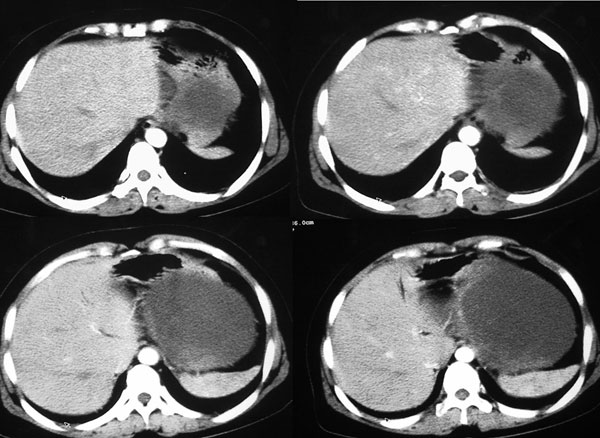

强化片

以下是引用守望可可西里在2006-8-30 10:57:00的发言:[br][br] 定位:胰腺体尾部。[br] 定性:胰腺囊腺癌可能性大。[br] 理由:胰腺体尾部呈多囊状分叶,部分病灶与前腹壁粘连,且下部形态不规则,毛糙不整、凸凹不平。囊壁厚薄不一致,多个大小不等壁结节突入,囊壁及壁结节明显不均匀强化。偏右侧囊内见液-液平面样相对高密度,呈与壁结节类似强化。性质:1.出血?2.壁结节?

以下是引用duguo在2006-8-30 12:13:00的发言:[br]支持胰腺囊腺癌诊断,建议穿刺活检.